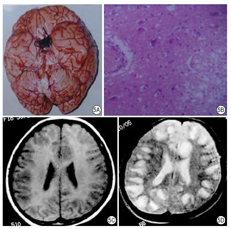

病理改变:非霍奇金淋巴瘤多侵犯大脑基底部、额叶、颞叶、顶叶、侧脑室旁,一般为单发局限性肿块,少数也可发生多中心生长,累及双侧大脑,病灶血供丰富,常有出血、坏死。如果病灶累及脑膜和脑室,才形成广泛浸润性病变,如果发生在脑室之内,则形成占位。脑淋巴瘤的病理特征为:①瘤细胞聚集在血管周围,呈袖套样排列,类似血管炎表现;②瘤细胞形态较一致,核染色较深,瘤细胞向周围组织浸润;③瘤细胞间可有散在吞噬细胞,呈"满天星"图像,吞噬现象比较明显;④瘤周脑组织可有不同程度的充血水肿,出血变性坏死,伴格子细胞及胶质细胞增生(图9A)。

影像表现:当淋巴瘤表现为脑室周围浸润病变时,增强扫描脑膜及脑室,室管膜明显强化,如果淋巴瘤在脑内形成占位,MR T1WI呈低信号,T2WI呈高信号。增强后肿块呈不均匀增强。中心多坏死,无强化,边缘呈"地图样"明显异常强化(图9B,图9C,图9D)。有报道称,脑脊液EB病毒DNA的PCR检查有助于淋巴瘤的诊断[14]。

病理改变:①HIV相关性脑动脉闭塞6 h以内脑组织改变尚不明显,8~48 h缺血的中心部位软化、组织肿胀、坏死。灰白质界限不清,出现脑梗死。镜检见组织结构混浊,神经细胞及胶质细胞变性、坏死、毛细血管轻度扩张。周围可见液体或红细胞渗出。动脉阻塞2~3天后,周围水肿明显;7~14天,病变区明显变软,神经细胞消失,脑组织开始液化,吞噬细胞大量出现,星形细胞增生;21~28天胶质细胞及毛细血管增生,小病灶形成胶质瘢痕,大病灶形成软化灶。②HIV相关性分水岭脑梗死病变部位多位于相邻血管供血区之间的分水岭区或边缘带。一般认为分水岭梗死多由于血流动力学障碍所致。③HIV相关腔隙性脑梗死为病变血管多为直径100~400 pm的深穿支动脉,故病灶多位于壳核、尾状核、内囊、丘脑、桥脑基底部及辐射冠等,病灶直径一般为0.2~15 mm,由于软化坏死组织被吞噬而残留小空囊腔,多个囊腔存在即腔隙状态。发病率相当高。(图10A、图10B)

影像表现:AIDS患者发生脑血管以外的因素很多,如HIV感染内皮细胞,使内皮细胞受损,可能诱发血栓形成,或免疫复合无聚集,使血管狭窄,在血管因子的作用下,使血管平滑肌和纤维母细胞增生,也可导致血管狭窄(图10C,图10D,图10E)。